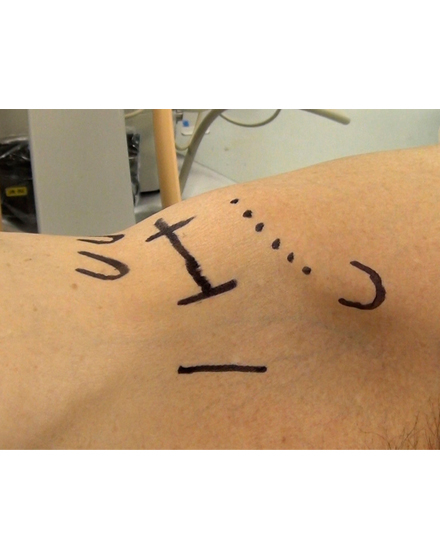

骨粗鬆症による背骨の骨折や転移性脊椎腫瘍(がんの背骨への転移)による病的骨折に対して世界中で行われている低侵襲な手術法です。日本では2011年に保険適用になり行われています。全身麻酔をして背中の約5mmの傷2カ所から細い針を骨折椎体に挿入します。その針を介して風船(Balloon)を骨折椎体内に設置し、ゆっくりと潰れた骨を整復・復元します。整復後に除去した風船のスペースに骨セメントを注入して、骨折を人工的に接合します。手術は約1時間程度で、手術直後から痛みが軽減することが多く、翌日より起立・歩行を開始します。入院期間は通常約3~7日程度になります。